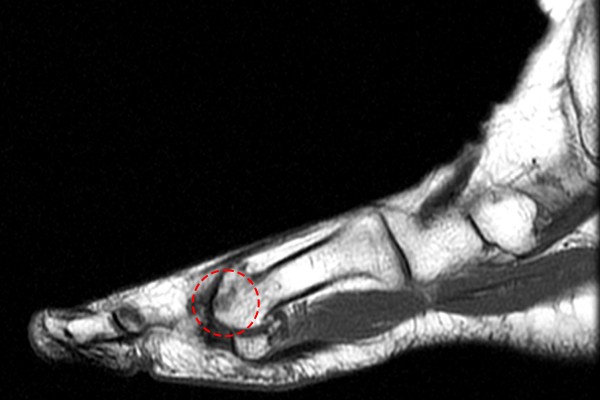

환자분의 발 상태를 확인하기 위해 X-RAY 촬영을 진행하였고, 정상적인 좌측 발과 비교했을 때, 우측 발 엄지 관절이 좁아져 있는 것이 확인되었습니다.

96707d45bfa78bc815f4e3f85a28a525_1757898743_5881.jpg